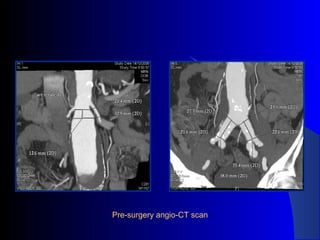

The document discusses the clinical application of the Endurant stent graft system in treating aorto-bisiliac aneurysms, detailing procedures performed on two male patients aged 72 and 73. Each patient had a history of dyslipidemia and carotid atherosclerosis, with procedures involving the bilateral bell bottom technique and the use of coils and fibrin glue. It includes pre-surgery imaging, intrasurgery angiography, and follow-up control scans to monitor outcomes.